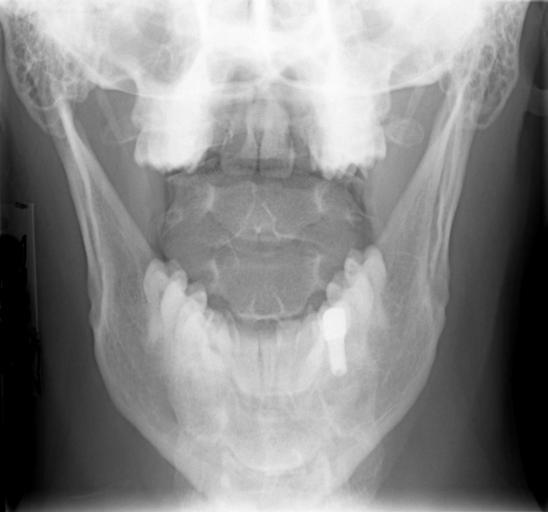

MAKE A MEME View Large Image Cervical Xray AP View.jpg en X-ray of cervical spine neck AP front view with mouth open to show C1-C2 This series of x-rays were part of pre-surgical evaluation to help identify spinal instability Patient is a 37 year old male with a ...

Keywords: Cervical Xray AP View.jpg en X-ray of cervical spine neck AP front view with mouth open to show C1-C2 This series of x-rays were part of pre-surgical evaluation to help identify spinal instability Patient is a 37 year old male with a history of multiple neck traumas with pain and muscle spasms and dental implant in lower jaw Excerpt from radiologist's report FINDINGS Five views of the cervical spine including flexion and extension were performed There is no evidence of fracture bone destruction or malalignment There are degenerative bone and is changes at C5-6 There is no evidence of cervical instability on the flexion and extension views The facet joints are well aligned Bony spurring is narrowing the C5-6 neural foramina bilaterally IMPRESSION Degenerative changes at C5-6 No evidence of instability Ragioagraphie aux raysons X du rachis cervical cou AP vue avant avec la bouche ouverte pour voir C1-C2 Cette série de radiographies faisaient partie de l'évaluation pré-chirurgicale pour aider à identifier une instabilité vertébrale Le patient est un homme de 37 ans ayant des antécédents de traumatismes multiples cou avec des spasmes et des douleurs musculaires et implant dentaire à la mâchoire inférieure Extrait du rapport du radiologiste RÉSULTATS Cinq vues de la partie cervicale de la colonne vertébrale ont été faites dont en flexion et en extension Il n'y a pas de signe de fracture de destruction osseuse ni de défaut d'alignement On observe un phénomène de gégénérescence osseuse des changements en C5-6 Il n'existe aucune preuve de l'instabilité du cou sur les radios montrant la flexion et l'extension Les facettes articulaires sont bien alignés Bony spurring is narrowing the C5-6 neural foramina bilaterally IMPRESSION Changements dégénératifs eu C5-6 Aucune preuve d'instabilité own medical image work for hire Stillwaterising 2010-04 File Cervical Xray Extension jpg File Cervical Xray Extension view jpg File Cervical Xray Lateral View jpg Magnification 0 4x converted from lossy DICOM file Cc-zero X-rays of the neck Mouths open